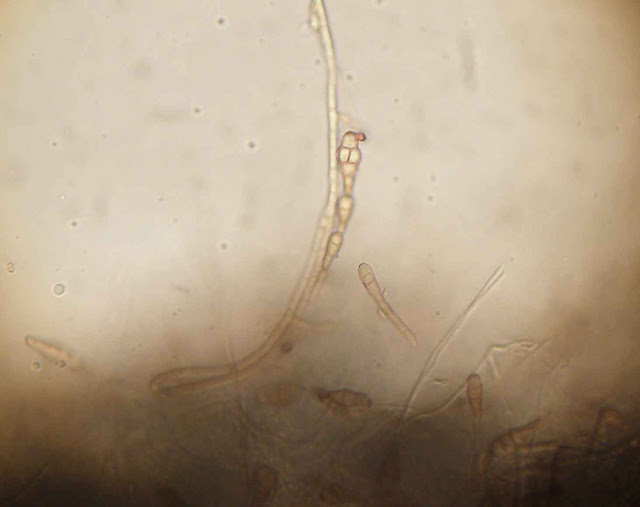

A estirpe isolada revelou na análise microscópica uma intensa e típica esporulação.

Conidia multicelular típica da  espécie.

Cadeia acropetal de conidias.

Cadeias de conideos multicelulares típicas. As cadeias podem ser simples ou ramificadas.

Hifas com pigmento castanho.